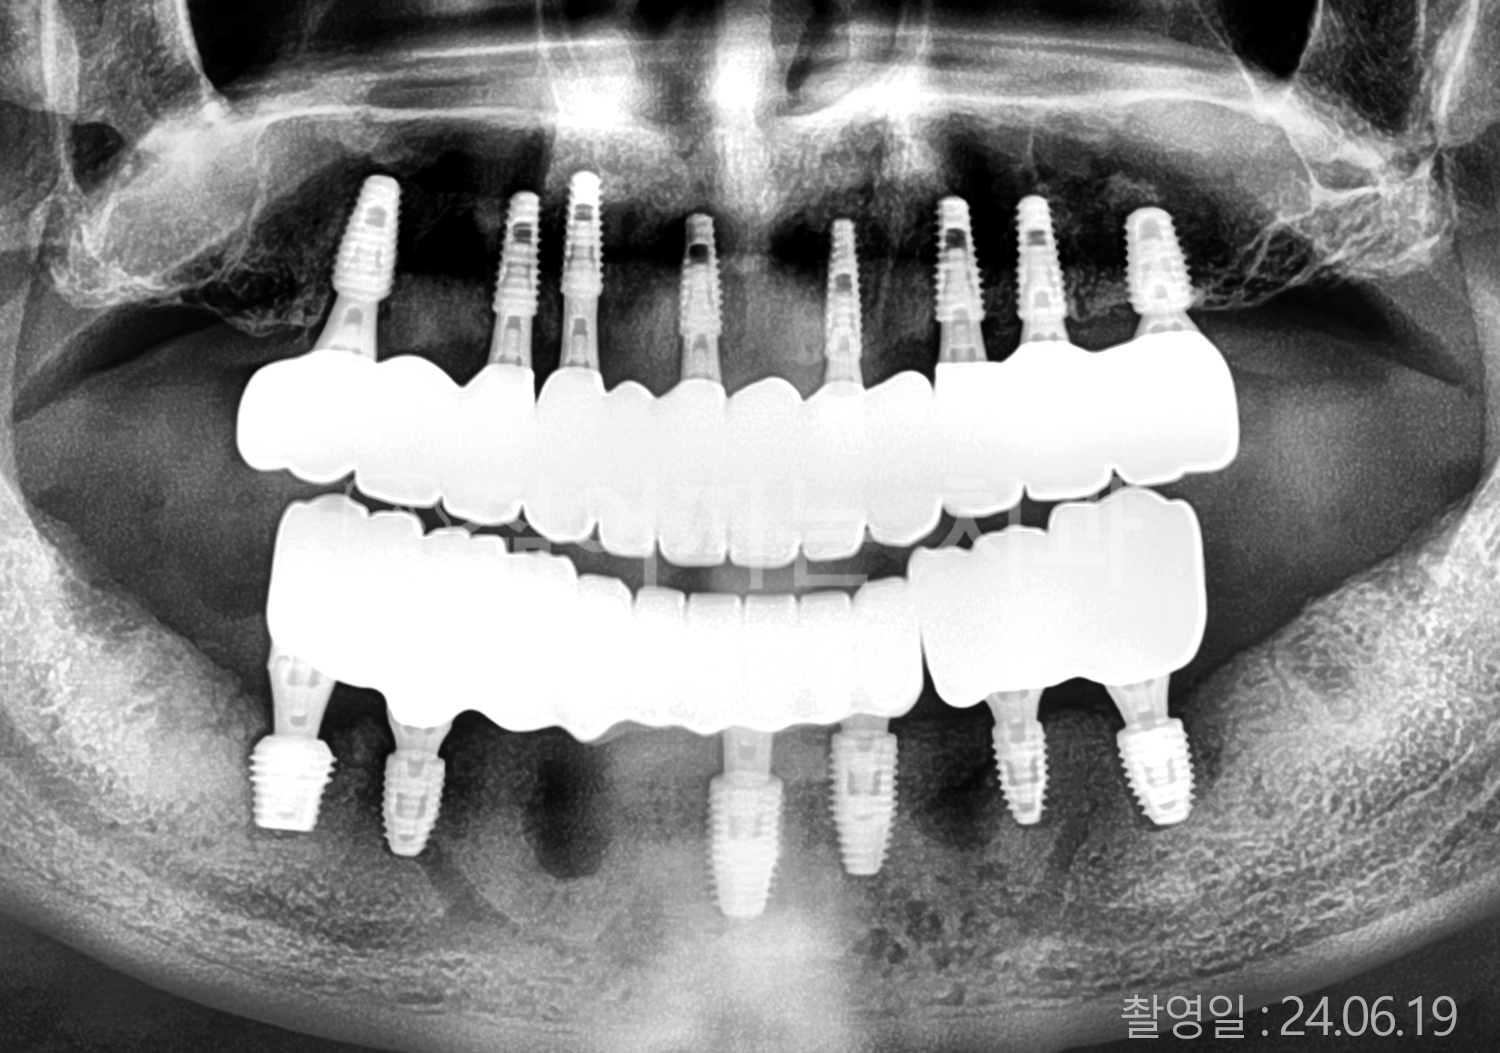

• 60대 전체치아 10개 이상 임플란트